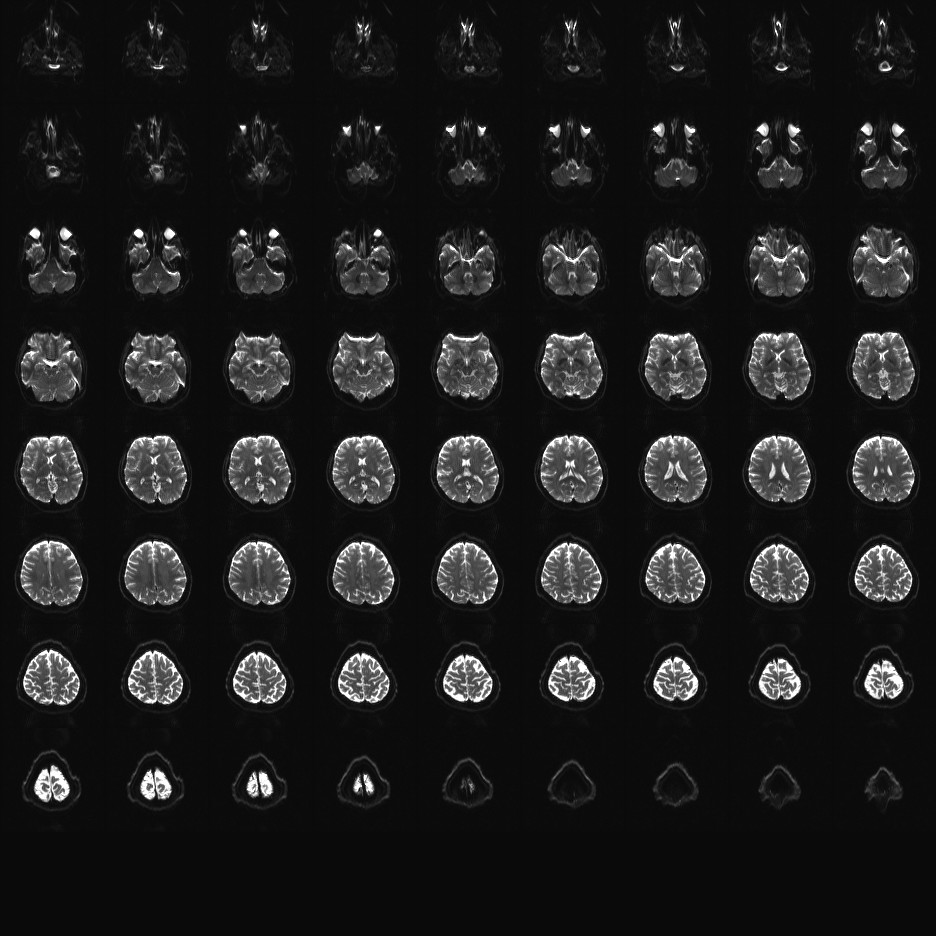

Multi-banded RF pulses can be used to accelerate volume coverage along the slice direction by simultaneously exciting and acquiring multiple slices and subsequently unaliasing them using parallel imaging principles and the spatial information available in multi-channel RF array coils.

This allows for a direct reduction in the volume TR by the number of simultaneously excited slices (i.e., the multiband (MB) factor or the slice acceleration factor).